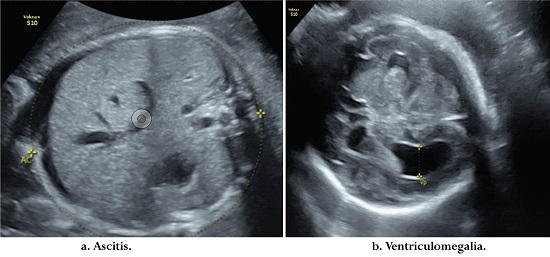

Mujer de 20 años que ingresó a la institución el 10 de octubre de 2019, estado civil soltera, oriunda y residente de Bogotá. Consultó al servicio de urgencias por actividad uterina con gestación de 30.2 semanas, sin otros síntomas. Antecedentes médicos negativos. Antecedentes gineco-obstétricos: 2 gestaciones, 1 partos, sin abortos previos, un hijo vivo. Paciente inició controles prenatales en semana 16, se documentó sífilis gestacional, se administraron 3 dosis de penicilina G benzatínica de 2,400,000 de unidades intramuscular. Se dio tratamiento a la pareja.

Examen físico: signos vitales en parámetros normales, frecuencia cardiaca 84 lpm, presión arterial 110 /66 mmHg. Frecuencia respiratoria 20, altura uterina de 29 cm fetocardia 134 lpm, al examen ginecológico: dilatación 4 cm con membranas íntegras. Se tomaron paraclínicos: hemograma: Hb: 11 gr/dl, creatinina: 0,5 mg/ dl, hepatitis B: negativa, prueba VIH: negativa, prueba treponémica rápida: positiva y VDRL: 64 diluciones. Se realizó el diagnóstico de caso probable de sífilis gestacional. Se considera reinfección y se formula penicilina benzatínica al compañero. Ultrasonido: biometría para 30 semanas. Crecimiento fetal normal. Líquido amniótico normal. Hídrops fetal: derrame pericárdico, ascitis; además de hepatomegalia y ventriculomegalia simétrica leve. Doppler de anemia cerebral media sin anemia (Figura 3). Se hospitalizó, se inició esquema de maduración pulmonar fetal, neuroprotección fetal con sulfato de magnesio, tocolisis con nifedipino. Evolución: el monitoreo fetal presenta desaceleraciones, se consideró estado fetal no satisfactorio y se decide cesárea por lo que no alcanza a iniciar el manejo para sífilis gestacional. Procedimiento sin complicaciones. Líquido amniótico fétido y cavidad hipertérmica. Se obtuvo recién nacido de sexo femenino de 1,260 gramos, Silverman de 6, requirió intubación endotraqueal y traslado a unidad de cuidados intensivos neonatales. La madre inició tratamiento con antibiótico: clindamicina y gentamicina por sospecha clínica de corioamnionitis, con evolución satisfactoria y se da salida al tercer día de puerperio. El recién nacido se hospitalizó para estudio y recibió tratamiento con penicilina cristalina endovenosa por 14 días, posteriormente se dio egreso sin complicaciones.